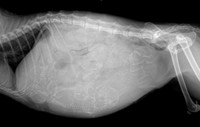

【写真】FIPの誤診リスクが増えている